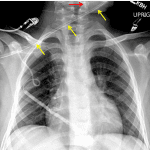

Indication: Sepsis, status post central line placement

- Right subclavian approach Broviac catheter with tip overlying the right atrium

- Enteric tube with tip overlying the upper neck

- No focal airspace opacification, pleural effusion, or pneumothorax

- Normal size and configuration of the cardiopericardial silhouette

- Malpositioned enteric tube

Right subclavian approach Broviac catheter with tip overlying the right atrium. No pneumothorax.

Enteric tube with tip overlying the upper neck. Recommend repositioning.

No focal airspace opacification or pleural effusion.

Normal size and configuration of the cardiopericardial silhouette.